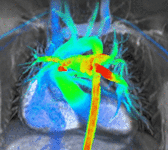

Conventional phase contrast imaging can be extended by applying flow-sensitive gradients in 3 orthogonal planes within a 3D volume throughout the cardiac cycle. Such 4D imaging encodes the velocity of flowing blood at each voxel in the volume enabling fluid dynamics to be visualised using specialist software. Applications are in complex congenital heart disease and for research into cardiovascular flow characteristics - however it is not in routine clinical use due to the complexity of post-processing and relatively long acquisition times.[26]

4D flow models. Intra- and extracardiac flow is visualised in a time-resolved 4D volume encompassing the heart and great vessels. Left: Flow velocity. Centre: Streamlines. Right: Flow vectors.